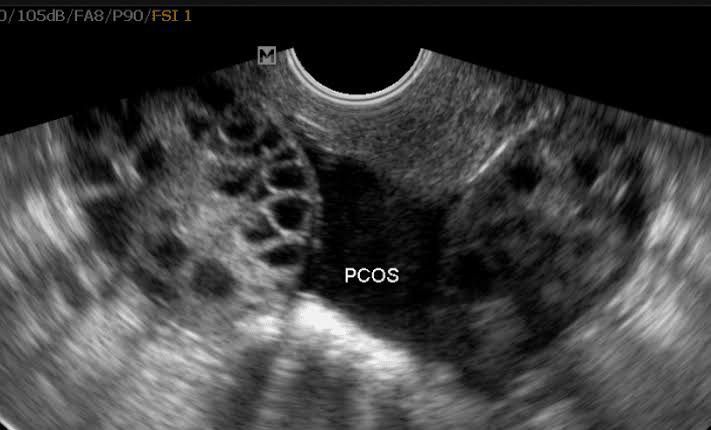

Polycystic ovary syndrome (PCOS) is a disorder characterized by abnormally high amount of androgens produced by the ovary. Women with PCOS presents with menstrual irregularities, large polycystic ovaries, hirsitusm, acne, infertility and acanthosis nigricans. PCOS is diagnosed by: 1. Ultrasound: 10 discrete follicles of less than 10mm peripherally arranged. 2. LH levels and FSH:LH ratio: Increased LH and FSH:LH ratio is seen 3. Increase in fasting insulin 4. Sex hormone binding globulin (SHBG) decreased. Picture credit: https://www.mireproductivemedicine.com/polycystic-ovary-syndrome-common-misunderstood/